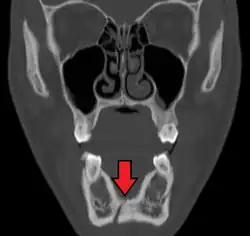

Traditionally, plain films of the mandible would be exposed but had lower sensitivity and specificity owing to overlap of structures. Views included AP (for parasymphsis), lateral oblique (body, ramus, angle, coronoid process) and Towne's (condyle) views. Condylar fractures can be especially difficult to identify, depending on the direction of condylar displacement or dislocation so multiple views of it are usually examined with two views at perpendicular angles.[11]

Panoramic radiography

Panoramic radiographs are tomograms where the mandible is in the focal trough and show a flat image of the mandible. Because the curve of the mandible appears in a 2-dimensional image, fractures are easier to spot leading to an accuracy similar to CT except in the condyle region. In addition, broken, missing or malaligned teeth can often be appreciated on a panoramic image which is frequently lost in plain films. Medial/lateral displacement of the fracture segments and especially the condyle are difficult to gauge so the view is sometimes augmented with plain film radiography or computed tomography for more complex mandible fractures.

Computed tomography

Computed tomography is the most sensitive and specific of the imaging techniques. The facial bones can be visualized as slices through the skeletal in either the axial, coronal or sagittal planes. Images can be reconstructed into a 3-dimensional view, to give a better sense of the displacement of various fragments. 3D reconstruction, however, can mask smaller fractures owing to volume averaging, scatter artifact and surrounding structures simply blocking the view of underlying areas.

Research has shown that panoramic radiography is similar to computed tomography in its diagnostic accuracy for mandible fractures and both are more accurate than plain film radiograph.[12] The indications to use CT for mandible fracture vary by region, but it does not seem to add to diagnosis or treatment planning except for comminuted or avulsive type fractures,[13] although, there is better clinician agreement on the location and absence of fractures with CT compared to panoramic radiography.[14]